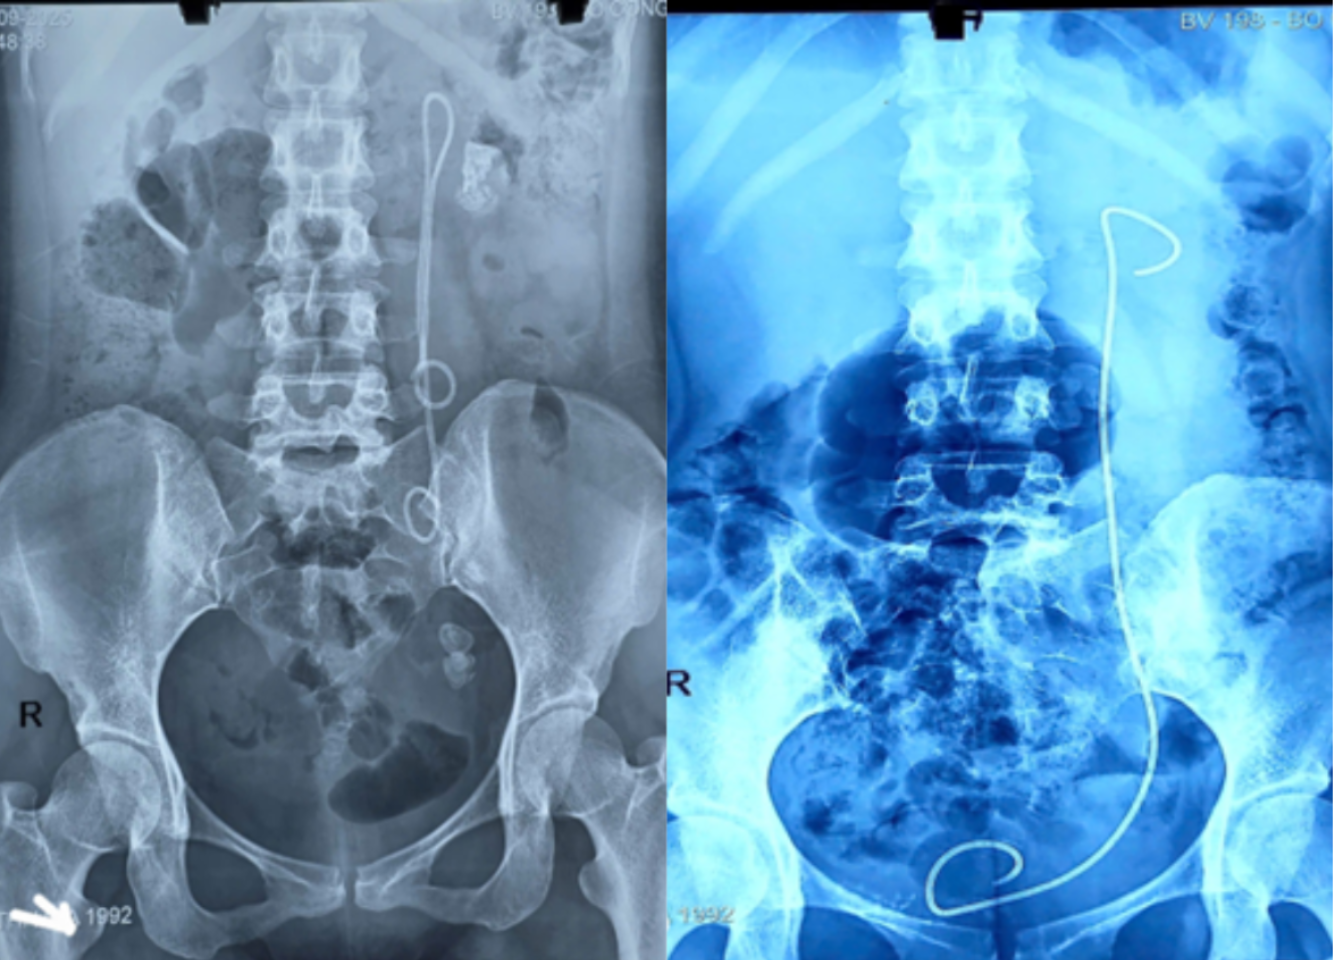

Hình ảnh phim chụp XQ trước và sau khi xử lý sỏi. Ảnh: BVCC

Trường hợp này, do Sonde JJ tồn tại tới 15 năm, bệnh nhân xuất hiện sỏi to ở nhiều vị trí, Sonde bám sỏi và di chuyển bất thường, khiến quá trình điều trị phức tạp và tiềm ẩn nhiều nguy cơ.